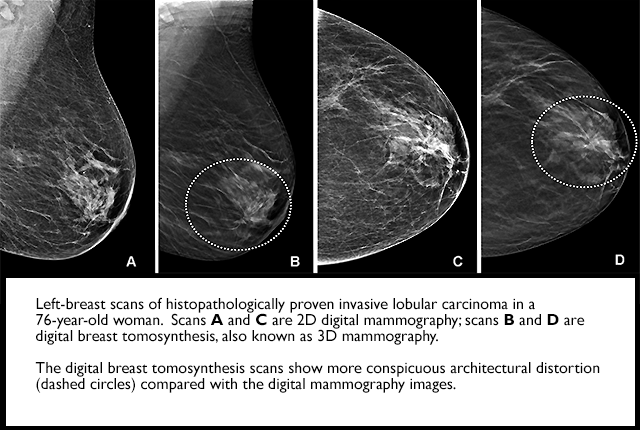

Researchers have found that digital breast tomosynthesis (DBT) has improved breast-cancer screening performance in community practice and identifies more invasive cancers, compared with digital mammography. In addition, radiologists’ interpretive performance has improved with DBT.

Compared with BCSC digital mammography screening exams from the same time period and previously published BCSC and National Mammography Database performance benchmarks, all performance measures were higher for DBT except sensitivity and false-negative rate, which were similar to concurrent and prior digital mammography performance measures.

“Radiologists appear to perform better with digital breast tomosynthesis and have higher accuracy on screening 3D mammograms than 2D mammograms across U.S. practices,” Lee noted. “As this becomes the mainstay screening modality, we hope to see improved screening outcomes for women.”